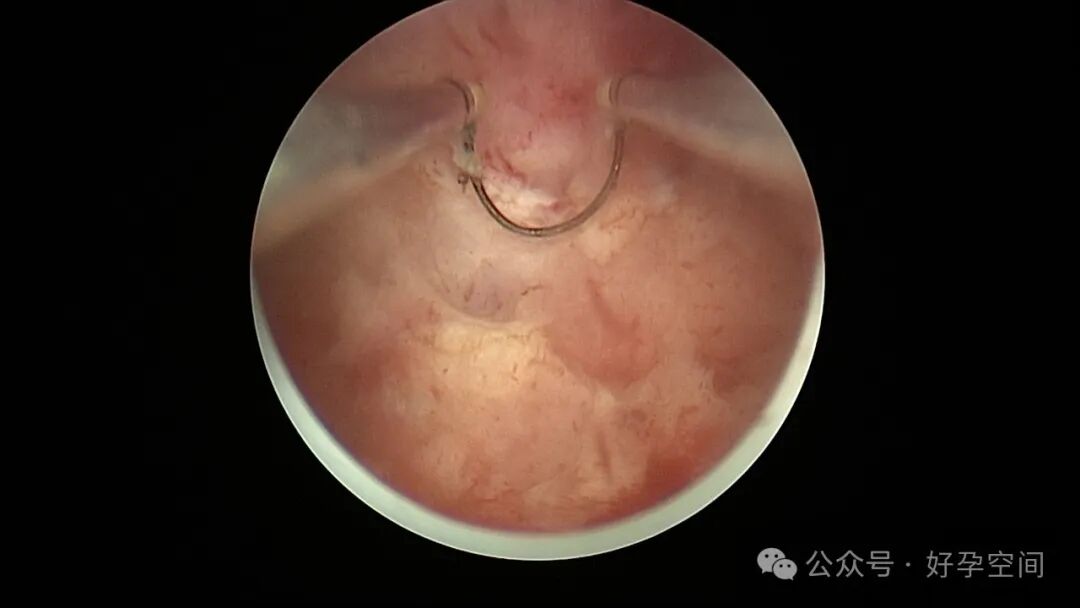

从以上病例可知,人流不全、药流不全有时候难以避免,宫内占位也并非都是胚物残留,门诊手术医生可能成为背锅侠。宫腔镜辅助下清宫可以最大限度地避免残留,及时发现宫腔内占位病变,切除送病检以明确诊断。